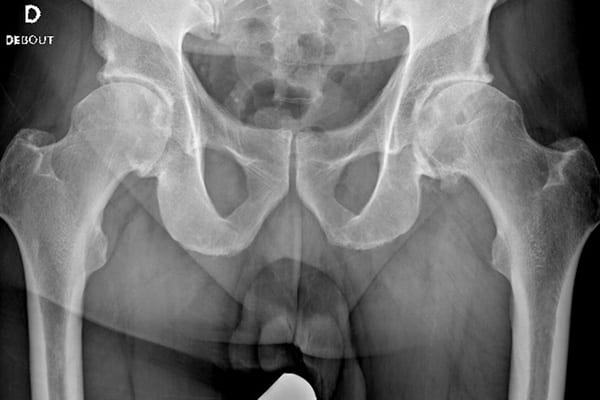

A terme, la coxarthrose, qui représente 10% des cas d’arthrose, induit une usure osseuse de l’articulation, au niveau de la tête du fémur et du cotyle. Des douleurs et un enraidissement font alors leur apparition, la marche devenant par ailleurs de plus en plus difficile.

L’articulation de la hanche est constituée de la tête du fémur et du cotyle. Lorsqu’ils sont trop usés, l’intervention consiste à les remplacer par une prothèse, après avoir procédé au nettoyage de la zone. L’objectif est de soulager la douleur, de redonner une mobilité normale à l’articulation et de permettre une reprise normale de la marche.

Une prothèse totale de hanche (PTH) est composée de deux parties. La première, sphérique, est insérée en remplacement de la tête, sur une tige, en haut du fémur. Pour sa part, la cupule cotyloïdienne, pièce hémisphérique creuse, est destinée à remplacer le cotyle, au niveau du bassin.